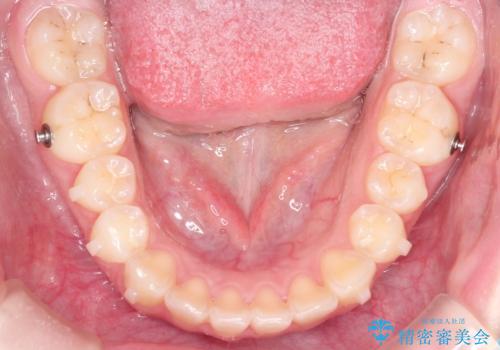

- 矯正装置

- インビザラン

- 治療期間

- 1年2ヶ月

上の奥歯を後方に移動させて、前歯を引っ込める計画としました。